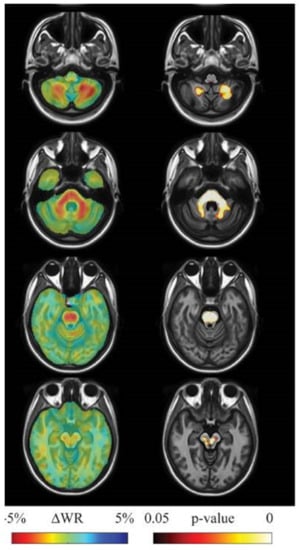

- Mascalchi, M.; Diciotti, S.; Giannelli, M.; Ginestroni, A.; Soricelli, A.; Nicolai, E.; Aiello, M.; Tessa, C.; Galli, L.; Dotti, M.T.; et al. Progression of brain atrophy in SCA2. A longitudinal TBM study. PLoS ONE 2014, 9, e89410. [Google Scholar] [CrossRef] [PubMed]

- Adanyeguh, I.M.; Perlbarg, V.; Henry, P.G.; Rinaldi, D.; Petit, E.; Valabregue, R.; Brice, A.; Durr, A.; Mochel, F. Autosomal dominant cerebellar ataxias: Imaging biomarkers with high effect sizes. NeuroImage Clin. 2018, 19, 858–867. [Google Scholar] [CrossRef] [PubMed]

- Mascalchi, M.; Marzi, C.; Giannelli, M.; Ciulli, S.; Bianchi, A.; Ginestroni, A.; Tessa, C.; Nicolai, E.; Aiello, M.; Salvatore, E.; et al. Histogram analysis of DTI-derived indices reveals pontocerebellar degeneration and its progression in SCA2. PLoS ONE 2018, 13, e0200258. [Google Scholar] [CrossRef]